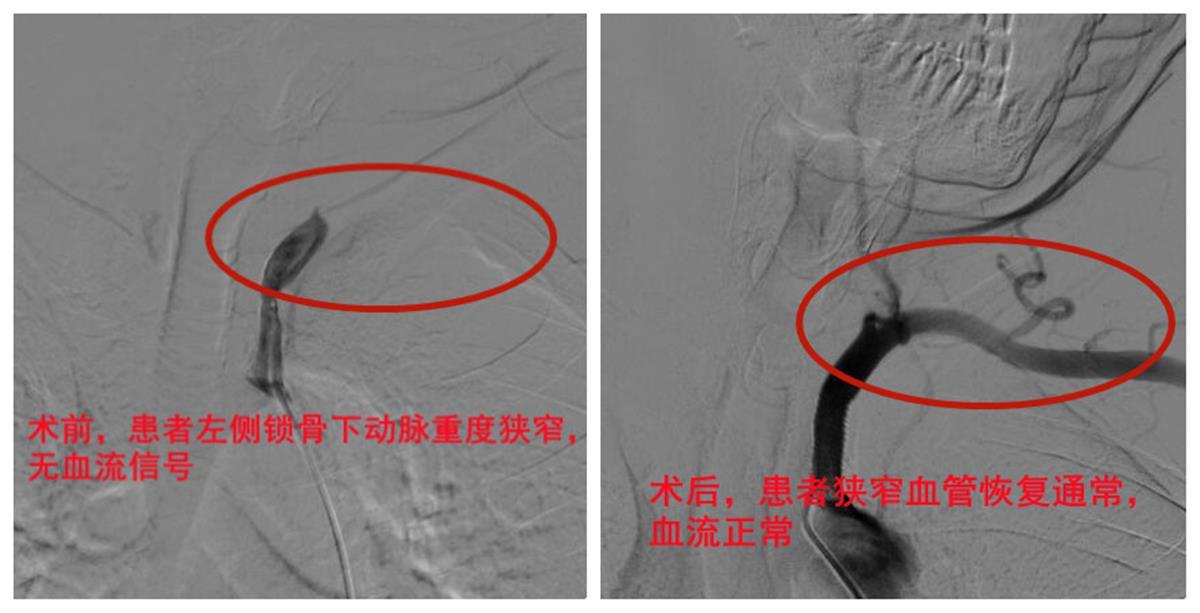

在邱先生及家属认可下,余稳带领手术医师谈宝珍等心血管介入团队联合麻醉团队,经邱先生右侧股动脉穿刺,巧借导管导丝精准定位到病变狭窄段血管,顺利植入一枚支架。术后造影显示,“罪犯”血管已完全恢复正常血流,两侧血压立即对称如常。

患者手术前后血管影像对比